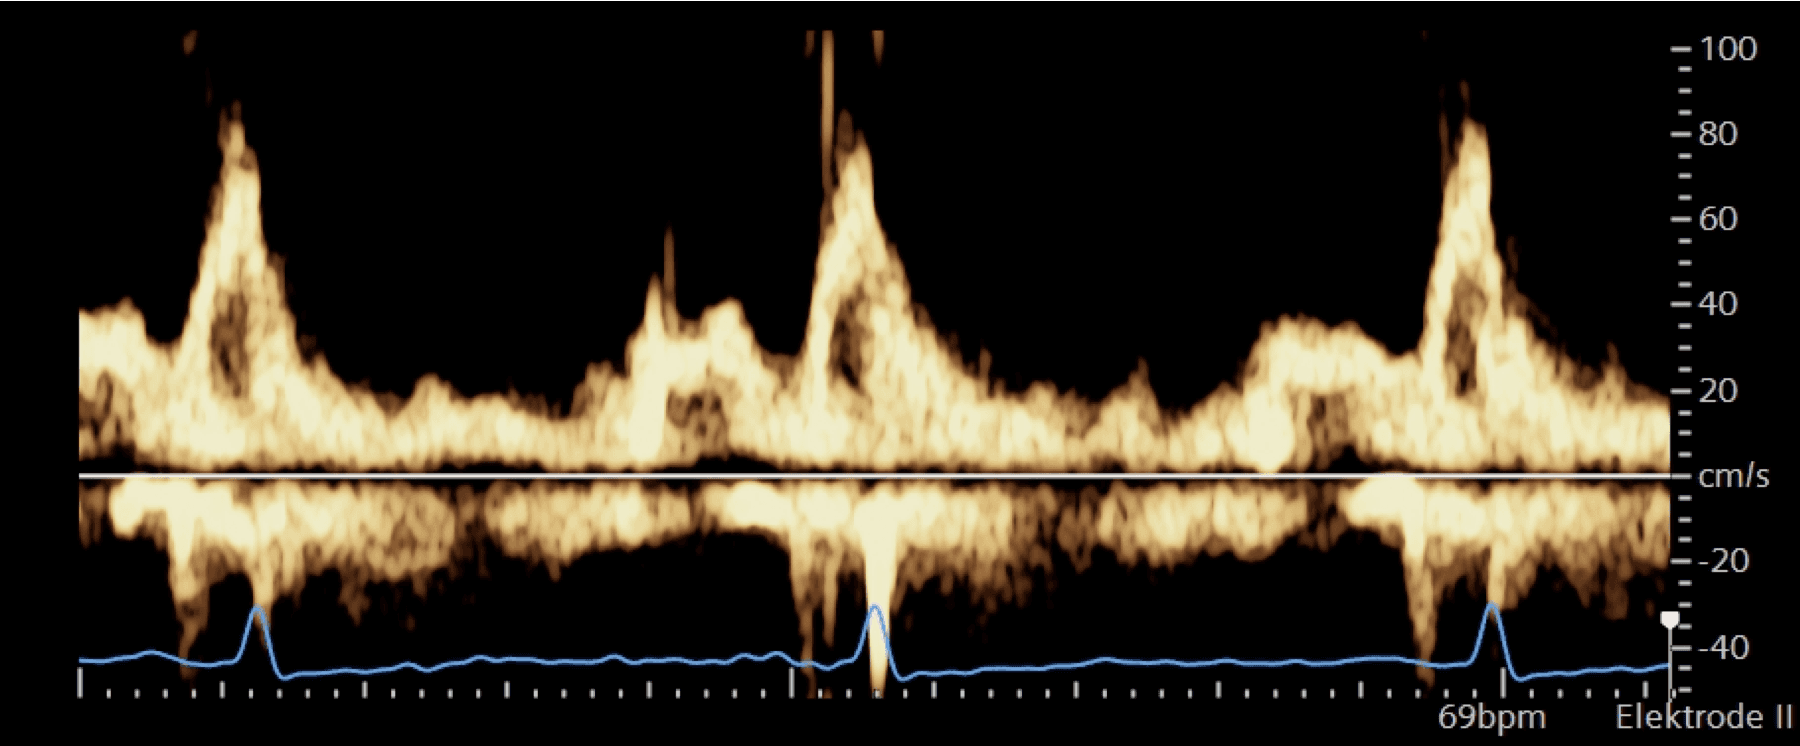

LV diastole

IVRT

AVC to MV-opening (MVO)

Isovolumic relaxation — compression & torsion lead to energy of the elastic elements of the cardiomyocytes & extracellular matrix in end-systole ➜ recoil & untwist in early diastole due to „relaxed state“ + active myocyte relaxation ➜ LV-volume ↑ & LV-pressure ↓ = measurable

At the beginning of diastole, LV pressures are just below AV pressures; the LV pressures are just above the LAP ➜ the IVRT is a short time interval of expansion of the LV without volume change ➜ AV & MV are closed = isovulmetric relaxation time (around 40ms)

Early filling (E-Wave)

Due to untwisting & relaxation, the LV pressure drops, LAP is higher than the LV pressure, the suction opens the MV ➜ end of the IVRT & beginning of the E-wave. A short (30-40ms) period lowers the LV pressure even though the LV volume expands ➜ a gradient from LA to LV ➜ flow acceleration

80-90% of the blood volume is sucked into the LV during this time (duration around 140ms)

Diastasis

The LV is in a relaxed state, LV pressures rise mildly, there is almost no pressure difference between the LA & the LV

The MV is „semi-open“

Heart rate dependent — bradycardia, long diastasis; tachycardia, almost no diastasis

Atrial contraction (A-wave)

LA contraction elevates LV pressures ➜ MV opens again, LV fills with blood again

In normal filling pressures, almost no „counterpressure“ from the LV, a little bit of blood flows back to the PV, 10-20% of the blood is transported with <5mmHg of pressure

The LVEDP, LAP, PV, and pulmonary pressures are low